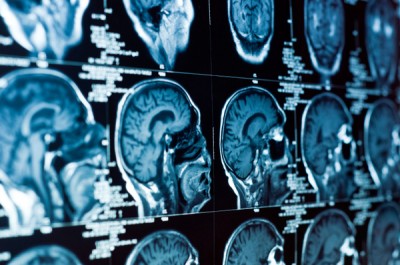

با استفاده از دستگاه های پرتونگاری پیشرفته و میکروسکوپ های قوی، پژوهشگران، قادر به مشاهده ی سلول های مغز و ارتباط آنها در محل پایانه های عصبی است.